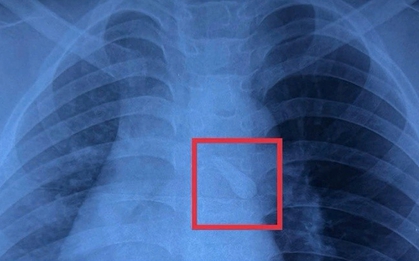

Một trường hợp y khoa gây sốc vừa được ghi nhận tại Tanzania: một người đàn ông 44 tuổi đến bệnh viện vì vùng ngực dưới núm vú phải chảy dịch mủ kéo dài 10 ngày. Bệnh nhân không hề sốt, không khó thở, cũng không có biểu hiện đau đớn nào bất thường.